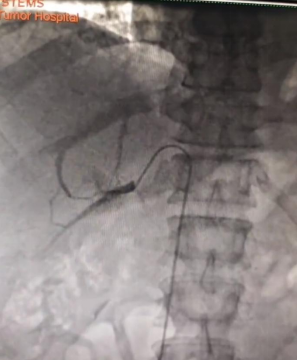

患者张某某,高血压20余年口服多种降压药无效,辗转多地来到我院就诊,经过MDT团队成员内分泌科王菊梅主任排查,发现双侧肾上腺腺体形态异常,随即启动肾上腺性高血压MDT协同诊疗流程。在完善了高血压五项、电解质、盐水负荷试验等一系列生化检查并初步诊断后,由西区介入科张正峰主任团队为患者实施了高难度的肾上腺静脉采血(AVS)介入手术,并即刻将多管新鲜血样通过“绿色通道”转送至检验科,李明主任团队接样后,快速检测来自双侧中央静脉和下腔静脉的皮质醇和醛固酮等指标,最终找到了患者20年来顽固性高血压的“元凶”——左侧异常分泌醛固酮的肾上腺小腺瘤。泌尿肿瘤外科在汇总MDT团队检查资料后,给出了明确的诊断,即原发性醛固酮增多症(PA)。随即由肾上腺肿瘤亚专业组徐华超主任为患者实施了微创的腹腔镜下左侧肾上腺肿瘤切除术。术后一周,患者血压和电解质恢复正常,康复出院。

图2、3 患者肾上腺静脉采血造影图片